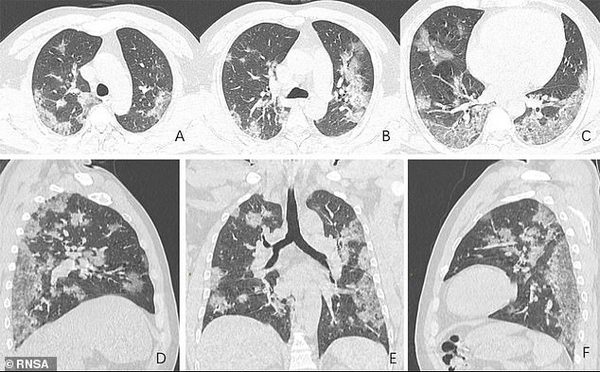

Так в сети появились рентгеновские снимки и сканы компьютерной томографии с изображением легких, которые принадлежали заболевшему коронавирусом. Радиологическое общество Северной Америки опубликовало снимки легких 44-летнего жителя Китая, работавшего на рынке в Ухане и умершего от COVID-19.

Китаец поступил в больницу в декабре 2019 года, поскольку около двух недель у него наблюдался сильный кашель и высокая температура. По итогу врачи диагностировали пневмонию и острый респираторный дистресс-синдром. Помочь пациенту не удалось, он скончался неделю спустя.

На фото видны все увеличивающиеся со временем белые пятна в нижней части дыхательных органов. Радиологи называют это симптомом "матового стекла", который отражает различные патологические изменения в легочной ткани.

Отмечается, что на фото заметно присутствие жидкости в легких мужчины, которое постепенно становится все более выраженным (проследить можно по изображению).